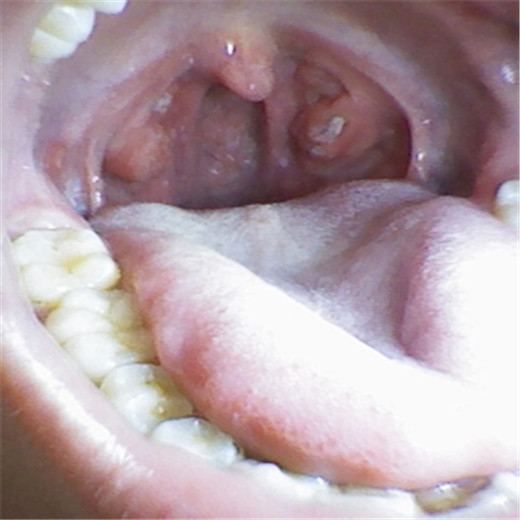

扁桃體炎圖片

扁桃體腫大